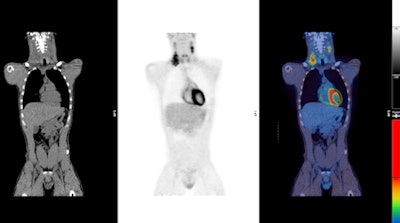

The role of FDG in a range of malignancies is established, but there are limitations to using FDG for imaging some tumors, they explained. Non-FDG tracers can be used to image a limited number of tumors, which are important for patient care, but the exceptions are the potential use of choline derivatives for imaging prostate cancer and the use of amyloid tracers for assessment of patients with cognitive impairment/dementia.